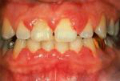

Il s’agit d’une inflammation et saignement des gencives occasionnés par l’accumulation de bactéries contenues dans la plaque et le tartre.

Expert Dental CareSi elle n’est pas

traitée, la gingivite peut se transformer en parodontite